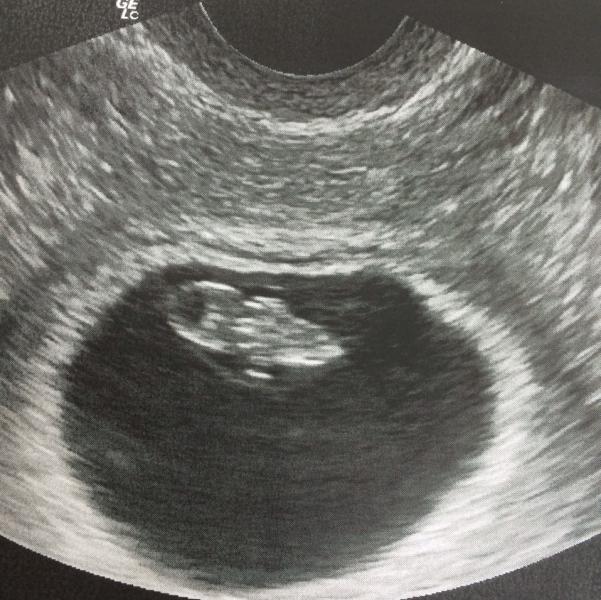

Ходила на узи. Оказывается, можно ничего не чувствовать, в плане недомогания и токсикоза, и при этом носить в себе жизнь. Слышала, как шуршит сердце, мною уже любимое:) шух-шух-шух:) чудо